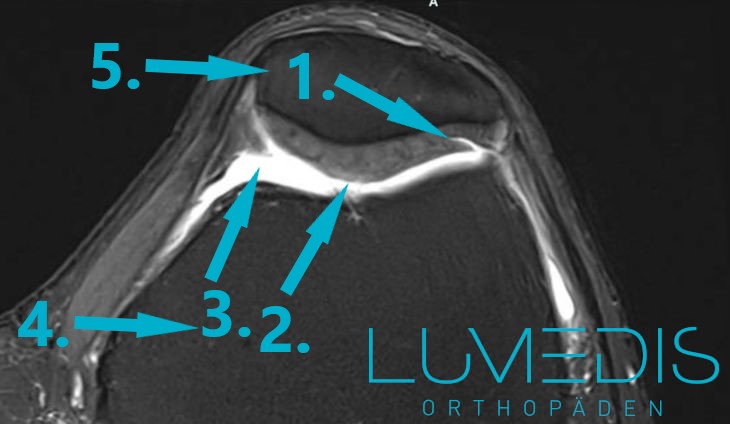

MRT der Kniescheibe (T2) - das Kniegelenk wird horizontal geschnitten (oben ist die Kniescheibe, unten geht es zur Kniekehle)

MRT Knie mit 4° Knorpelschaden

MRT mit Knorpelschaden hinter der rechten Kniescheibe

MRT mit einem Knorpelschaden hinter der Kniescheibe